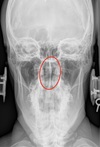

LATERAL CERVICAL LANDMARKS lateral cervical view

external acoustic meatus

Lateral cervical view

mastoid process (air cells)

A

Lateral cervical